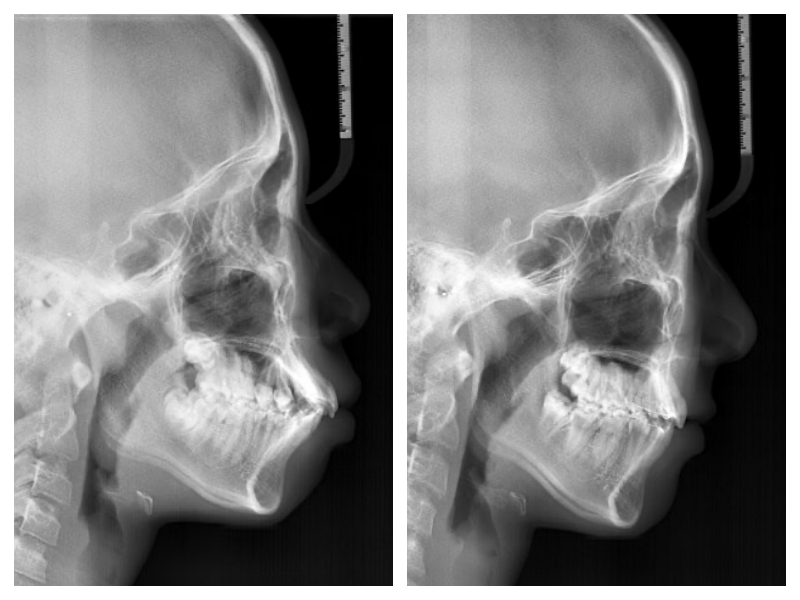

발레리나 친구들~ 무대에 서는 친구들이라 외모에 민감하고 특히 돌출과 비대칭때문에 사진 찍을 때 신경이 많이 쓰인다고 했다. 사실 골…